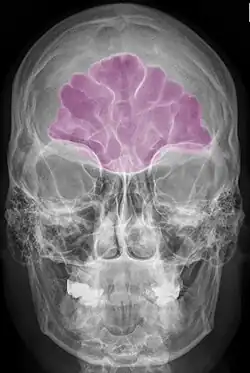

Stirnhöhle violett

Die Stirnhöhle (Sinus frontalis) ist eine der Nasennebenhöhlen (Sinus paranasales). Sie stellt einen mit Schleimhaut ausgekleideten Hohlraum im Stirnbein (Os frontale) dar, der mit dem mittleren Nasengang („Sinusgang“) der Nasenhöhle in Verbindung steht. Zusätzlich besteht eine Verbindung zu den Siebbeinzellen, die bei Pferden besonders geräumig ist, so dass beide Nebenhöhlen bei dieser Tierart auch als Sinus conchofrontalis zusammengefasst werden. Die Stirnhöhlen beider Seiten sind durch eine dünne Scheidewand (Septum sinuum frontalium) voneinander getrennt.

Ausmaß und Form der Stirnhöhle sind großen Schwankungen unterworfen. Dies gilt nicht nur für den Vergleich zwischen verschiedenen Spezies, sondern beim Menschen auch zwischen verschiedenen Individuen. Es sind für den Menschen vier Grundformen beschrieben: Bohnen-, Blatt-, Mitral- und Pyramidenform. Die Größe der menschlichen Stirnhöhle schwankt zwischen 0,05 und 7,8 cm3, nicht selten ist die Stirnhöhle gar nicht (Aplasie) oder nur gering (Hypoplasie) ausgebildet.[1] Auch das knöcherne Dach der Augenhöhle kann in variablem Ausmaß durch die Stirnhöhle pneumatisiert sein.[2]